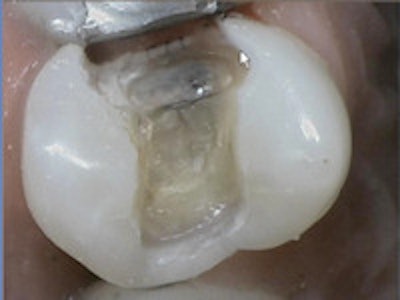

Here is a SonicFill restoration. This entire preparation was filled in a single increment, light-cured, and polished.

A SonicFill restoration that was filled in a single increment, light-cured, and polished.I have had no incidences of sensitivity and can easily say that I am thoroughly impressed with the SonicFill system.